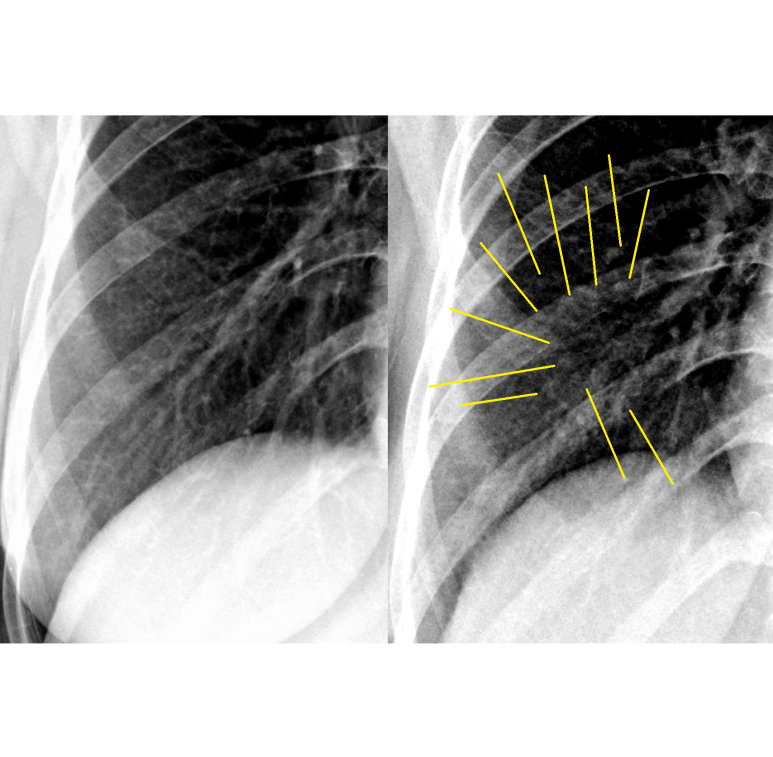

이번에 찍은 우측 사진이 미묘하게 전반적으로 지저분하다.

확대하고 음영을 변경해보면 다수의 결절성 변화, nodular 및 그 사이에 선상 음영들도 증가해 보인다. 0/1, 이상없다/이상하다의 판단이 필요

; reticulonodular pattern의 변화

엑스레이에 변화가 있다고 생각되니 <<>> 증상이 의미있어 보인다.

바이러스 폐렴을 고려.. 고열이었고, 호흡증상이 있어 응급실 방문하여 평가/판단을 받도록 하였다.

외주업체 판독은 정상 (재확인/문의하지는 않았다.)

최근 과거 사진과 비교하여 미묘한 변화가 있다 vs. 없다.